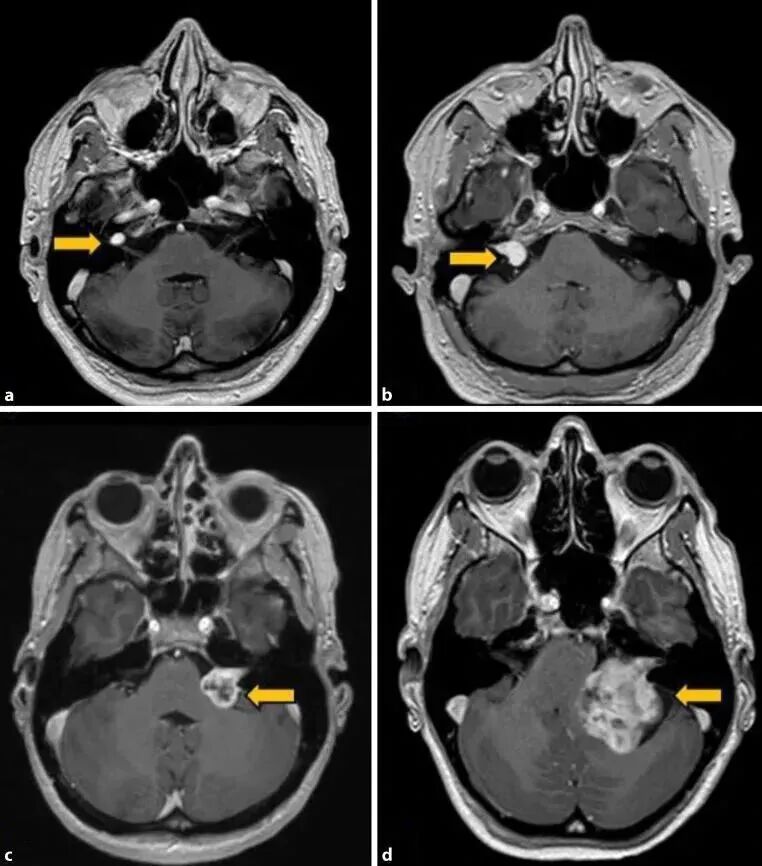

影像学检查:排除致命性病变

并非所有患者都需常规进行影像学检查,但出现以下情况必须排查:

单侧听力骤降伴眩晕、耳鸣持续加重、听力下降超过1周无改善。推荐优先选择内耳MRI,其能清晰显示听神经瘤、内耳血管病变等微小病灶;颞骨CT则可排除内耳骨折、先天性畸形等器质性问题。

需要注意的是,临床数据显示,约5%的“突聋”患者经MRI检查后确诊为听神经瘤等占位性病变。

图源网络

听神经瘤 | 多伴单侧渐进性耳鸣,MRI可见内听道扩大或肿瘤病灶 |